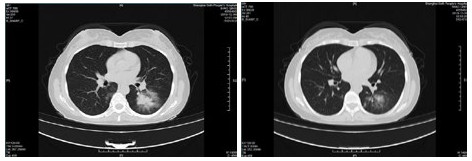

| 图 4 患者,男性,59岁,湖北籍,春节回乡探亲返沪,发热2 d入院,体温37.8℃, 乏力,既往体健。血白细胞总数及淋巴计数正常,甲型、乙型流感筛查阴性,新型冠状病毒核酸检测阳性。肺部CT提示双肺多发磨玻璃结节,病灶贴近胸膜伴支气管充气征及血管充血、增粗,可见部分纤维条索影 Fig 4 Case 4, male, 59 years old, born in Hubei Province, returned to Shanghai during the Spring Festival. He was hospitalized 2 days after fever, with a body temperature of 37.8℃ with fatigue. Normal WBC and lymphoid count, negative influenza A and B virus screening, positive novel coronavirus nucleic acid test. Lung CT showed multiple ground glass nodules in both lungs. The focus was close to the pleura, accompanied by bronchiectasis, hyperemia and thickening of blood vessels. Some fibrous bands could be seen |

| 图 5 患者,女性,44岁,沪籍,发病前10 d内有与确诊NCP患者接触史。出现发热,体温38.5℃,乏力,伴肌肉酸痛,既往体健。血白细胞总数及淋巴计数正常,甲型、乙型流感筛查阴性,新型冠状病毒核酸检测阳性。肺部CT提示双肺多发磨玻璃结节,病灶贴近胸膜伴支气管充气征及病变内血管充血、增粗 Fig 5 Case 5, female, 44 years old, born in Shanghai, had contact history with NCP patients within 10 days before the onset of the disease. Her body temperature was 38.5℃, with fatigue, muscle ache, previous physical fitness. Normal WBC and lymphoid count, negative influenza A and B virus screening, and positive novel coronavirus nucleic acid test. Lung CT showed multiple ground glass nodules in both lungs. The lesions were close to the pleura with bronchiectasis and congestion and thickening of blood vessels in the lesions |